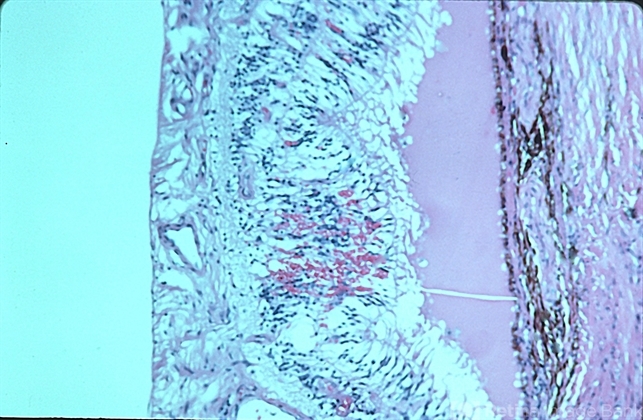

- meningioma, pathology

- Pathology.